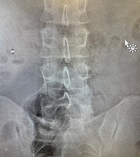

Рис. 6. Вид операционной раны на коже вблизи рубца (между разрезами кожи справа – отмечен стрелочкой) от входного отверстия от осколка. Рентген-контроль после удаления осколка и вид раны в конце операции с асептической повязкой.